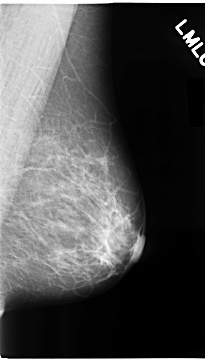

C_0100_1.LEFT_MLO

LEFT_MLO LINES 4704 PIXELS_PER_LINE 2664 BITS_PER_PIXEL 12 RESOLUTION 50 NON_OVERLAY